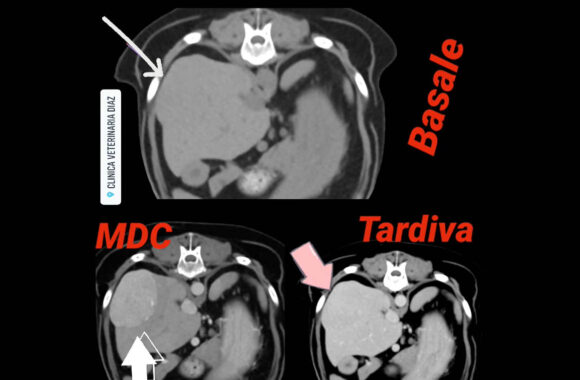

Il Servizio Tac Veterinaria a Portici

Attualmente l’unica clinica veterinaria di Napoli e provincia che ha a disposizione una TAC Multistrato da 128 strati in struttura, ultra veloce (total body in meno di 15 sec.), con refertazione in 24h/48h.